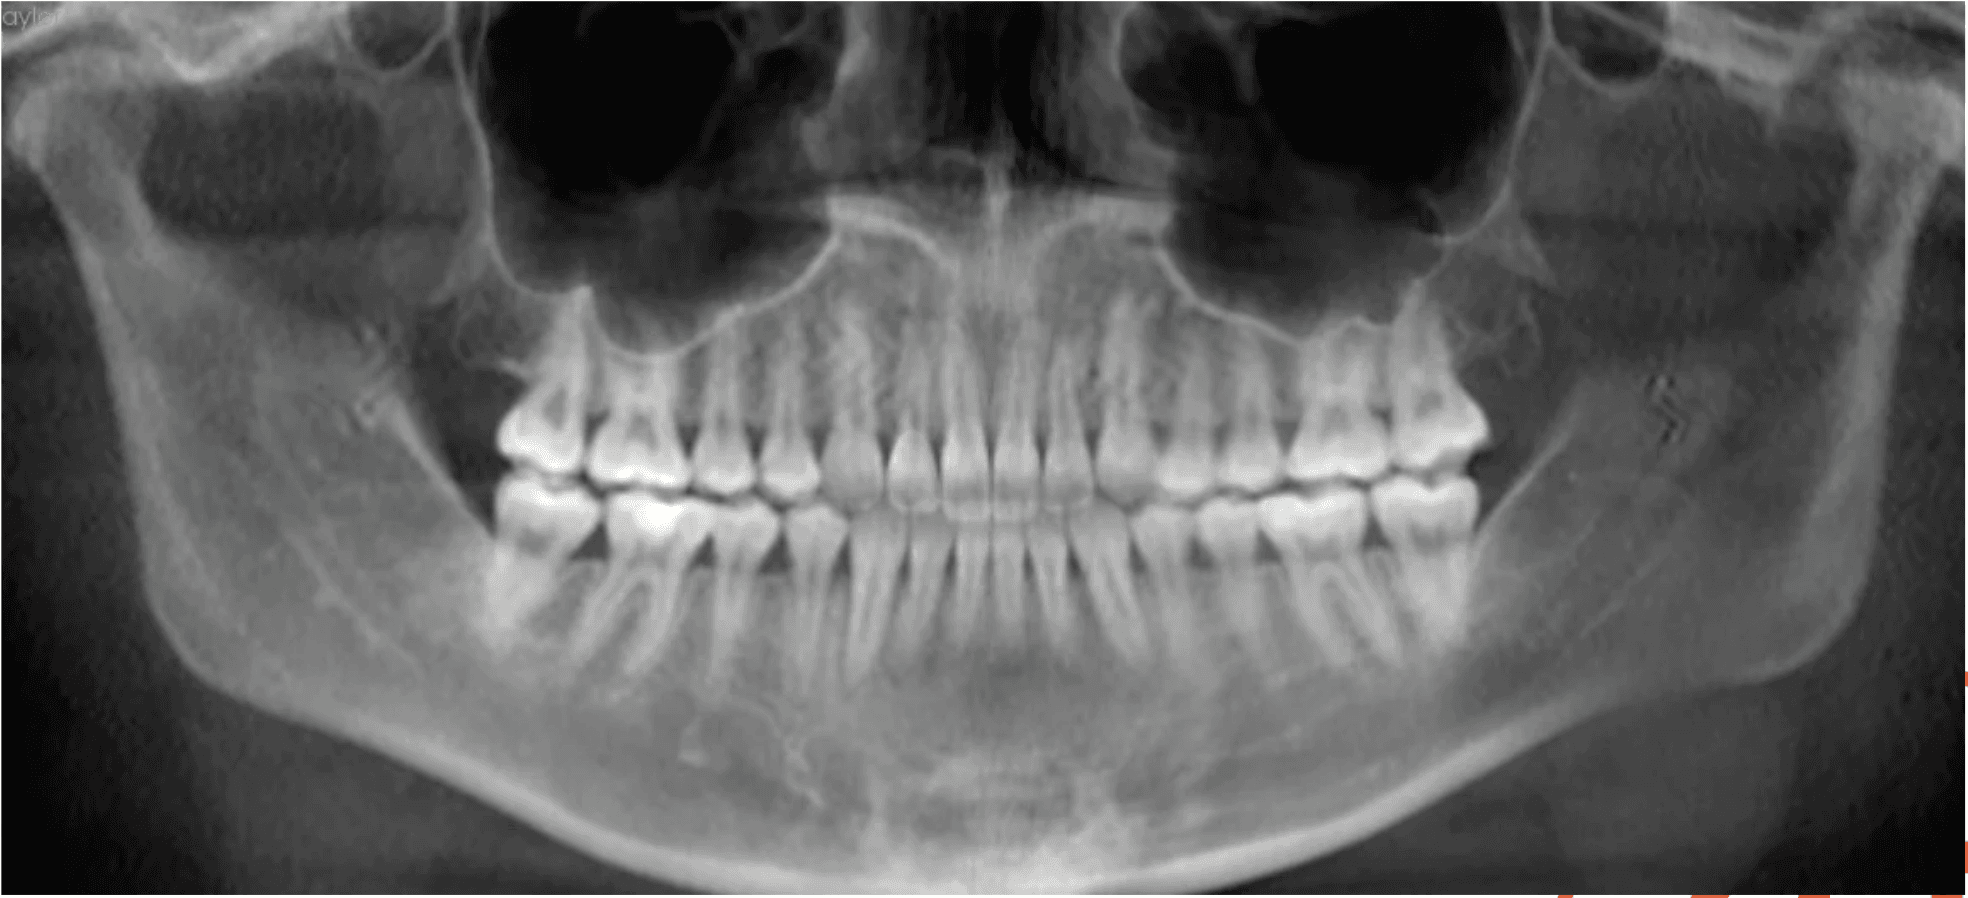

X-RAYS